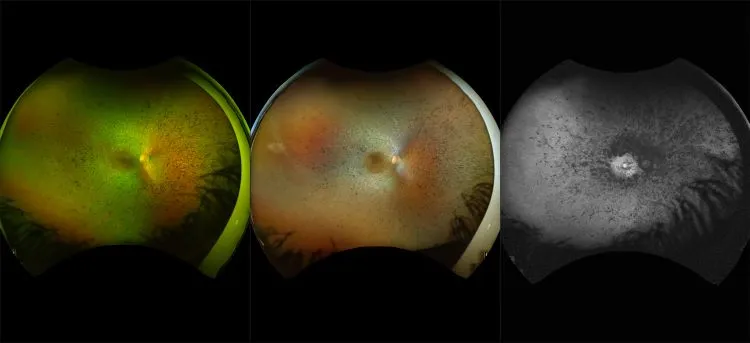

optomap® Recognizing Pathology

This material is designed as a searchable reference resource to support clinical decision-making. The information contained here should be used as general guidance when viewing optomap and OCT images from Optos devices. The differential diagnosis should be made under the direction of the responsible physician. These images were taken on the latest ultra-widefield optomap devices.

The Cases and Images

optomap Recognizing Pathology is searchable by pathology and/or optomap image modality. You may search by multiples of each selection. Each individual case is represented by the accompanying thumbnail image. Most cases include several different optomap image modalities. To view a full description of the case, please click on the thumbnail. Each image in the case will be made available through our OptosAdvance software which provides multi-dimensional visualization of digital images to aid in the analysis of anatomy and pathology. Support and pathology definitions can be found by selecting one of the buttons, above. Should you have questions, please complete the form below.